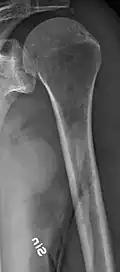

The diagnostic examination of a person with suspected multiple myeloma typically includes a skeletal survey. This is a series of X-rays of the skull, axial skeleton, and proximal long bones. Myeloma activity sometimes appears as "lytic lesions" (with local disappearance of normal bone due to resorption) or as "punched-out lesions" on the skull X-ray ("raindrop skull"). Lesions may also be sclerotic, which is seen as radiodense.[76] Overall, the radiodensity of myeloma is between −30 and 120 Hounsfield units (HU).[77] Magnetic resonance imaging is more sensitive than simple X-rays in the detection of lytic lesions. An MRI may supersede a skeletal survey, especially when vertebral disease is suspected. Occasionally, a CT scan is performed to measure the size of soft-tissue plasmacytomas. Nuclear Medicine Bone scans are typically not of any additional value in the workup of people with myeloma (no new bone formation; lytic lesions not well visualized on nuclear bone scan).

X-ray of the forearm, with lytic lesions -

Multiple myeloma in the upper arm -

Femur with multiple myeloma lesions -

Same femur before myeloma lesions for comparison -